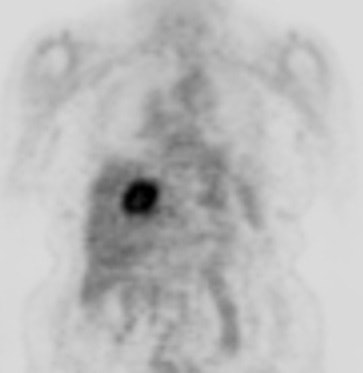

Cholangiocarcinoma: The patient below had a large cholangiocarcinoma. FDG PET imaging demonstrated markedly increased tracer uptake by the mass. There was no evidence of metastatic disease on PET imaging and the patient demonstrated a dramatic response to chemotherapy. |